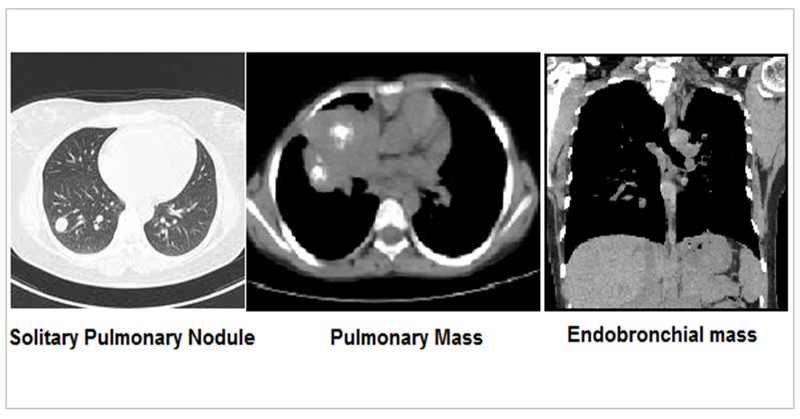

Bronchogenic carcinoma in early stages may present as a solitary pulmonary nodule (SPN) defined as a discrete, well-emarginated, rounded opacity less than or equal to 3 cm in diameter that is completely surrounded by lung parenchyma, does not touch the hilum or mediastinum, and is not associated with adenopathy, atelectasis, or pleural effusion.

Lung malignancy may also present as a pulmonary mass which are larger than SPN. SPN and masses are described as per size, shape, enhancement, boundaries, calcification, satellite lesions, other lobe, opposite lung, rib, lymph node and pleural involvement. Endobronchial involvement results in a positive bronchus sign. Multiple metastases from a distant malignancy to the lung presents as classical cannon ball metastasis.